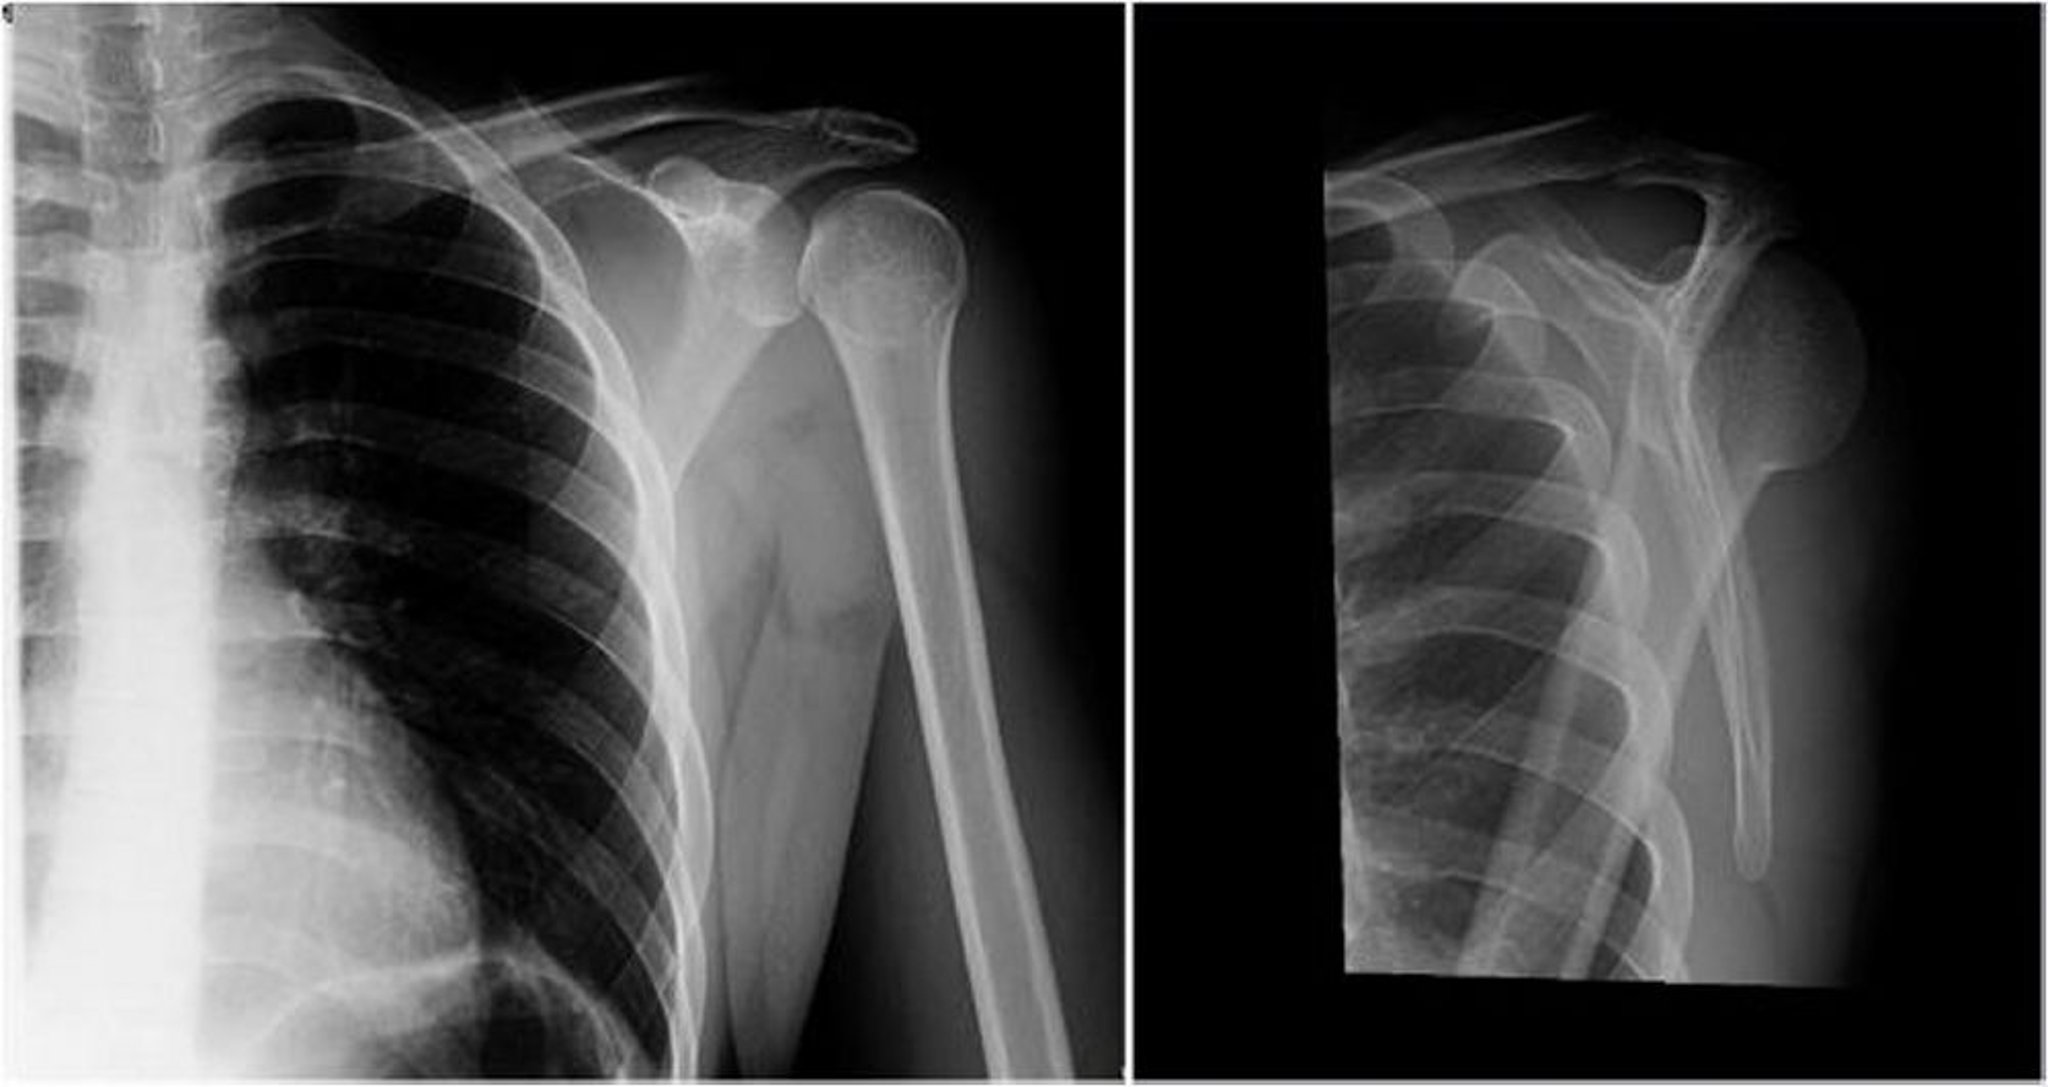

Задній вивих плечового суглоба: передньо-задня та Y-проекції

На лівому зображенні (передньо-задня проекція) голівка плечової кістки обернена всередину, що надає їй вигляду лампочки або конусу морозива (більша та менша горбистості плечової кістки не візуалізуються), що свідчить про задній вивих плеча. На правому зображенні (Y-проекція) голівка плечової кістки знаходиться дозаду відносно суглобової ямки, що свідчить про задній вивих плеча.

Знімок люб'язно надано лікарем Даніелем Кампаньє [Danielle Campagne], MD.